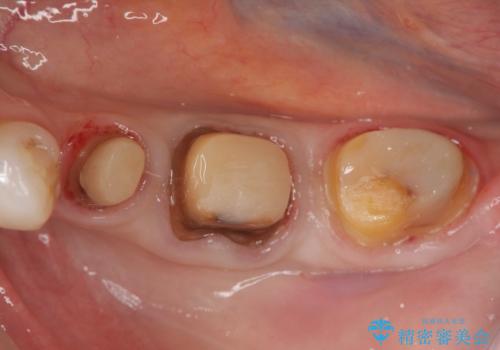

- 虫歯治療、老朽化した銀歯や詰め物 コンポジットレジンのやりかえを希望され来院されました。

クラウンやレジン下に再発していた虫歯を丁寧に除去したのち、歯ぐきの腫れが改善が見られないため歯周外科を行い歯ぐきの状態を整えたのちにジルコニアクラウンを製作していきます。